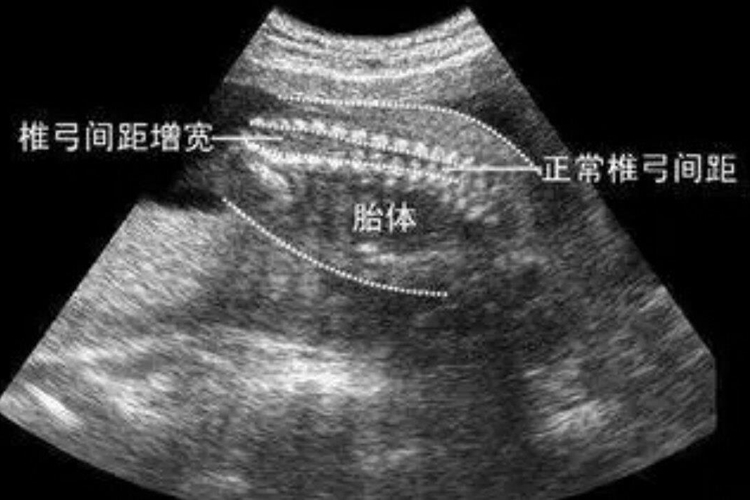

大排畸是在妊娠20-24周通过超声检查,判断胎儿是否存在脊柱椎弓间距增宽、软腭裂、心脏增宽等发育畸形情况。

大排畸通常在妊娠20-24周时进行的胎儿系统超声检查,筛查胎儿结构畸形。正常情况下胎儿心、脑、肾、膀胱、胃、上唇、四肢骨、脊柱、腹壁等均正常。当出现侧脑室增宽、脊柱椎弓间距增宽、软腭裂、双肾增大、心脏增宽、裂腹畸形伴肠管外翻等异常情况时,多提示胎儿发育异常。